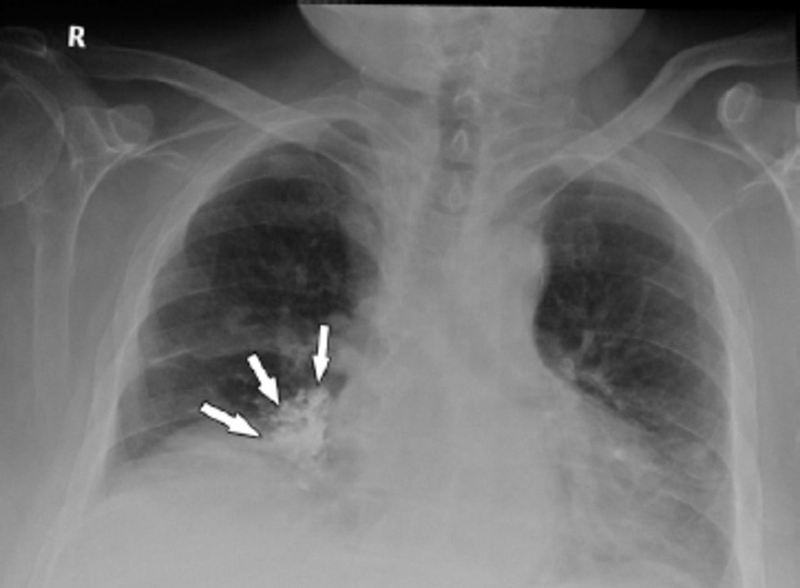

Khi hình chụp X quang của người bệnh hiển thị các vết mờ ở phổi, các bác sĩ sẽ phân tích hình thái vết mờ ở các phương diện như hình dáng, kích thước, đường bờ… Những yếu tố này kết hợp với thông tin về tiền sử bệnh lý, thói quen sinh hoạt, đặc thù công việc… sẽ làm căn cứ để bác sĩ đánh giá các nguy cơ mắc bệnh. Chụp X quang phổi có vết mờ phản ánh các trường hợp như sau:

Khi xơ phổi tiến triển cũng sẽ hình thành nốt vôi hóa quanh khối cơ. Nốt mờ trên hình chụp X quang phổi trong trường hợp này có thể là dạng chấm, dạng lưới hoặc dạng đơn độc. Nốt mờ dạng chấm hoặc dạng lưới có thể cảnh báo ung thư phổi nguyên phát (chiếm khoảng 6% trường hợp mắc bệnh). Vết mờ dạng đơn độc nằm ở trung tâm xơ phổi thường là nốt lành, còn được gọi là u hạt nhiễm trùng lao. Nếu xuất hiện dạng ổ nhiều nốt mờ, người bệnh có thể bị viêm phổi hoặc nhiễm khuẩn lao hg 0++3.